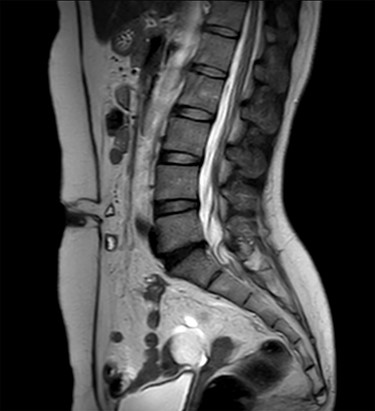

A 47-year-old woman was referred to us by her obstetrician. She developed a PHS after laparoscopic total hysterectomy with right oophorectomy performed 3 years previously. She reported pain with intermittent bulging on the superior aspect of the umbilical region. Clinical examination revealed a single hernia orifice at that location. Her height was 161.1 cm, with a weight of 60.1 kg, yielding a body mass index of 23.16 kg/m2. Her medical history included uterine fibroids and ovarian cysts. She had no history of smoking. Magnetic resonance imaging (MRI) revealed protrusion of adipose tissue at the upper side of the umbilical region, through a fascial defect measuring 9 × 13 mm; diastasis recti was also noted (Figs 1 and 2).

The patient did well after surgery. Follow-up MRI taken 10 days after surgery confirmed the absence of hernia and closure of the fascial defect (Figs 9 and 10).